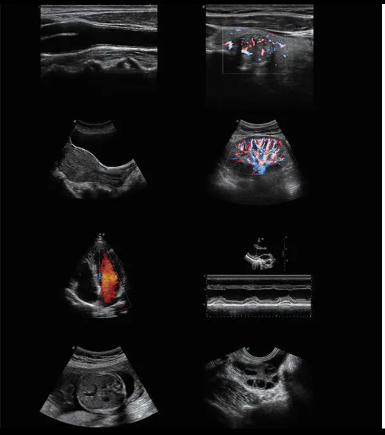

High-Resolution Imaging: Clear grayscale and Color Doppler imaging for accurate diagnosis

Advanced Doppler Technology: Color, Power, and PW Doppler modes

Wide Clinical Applications: Abdomen, OB/GYN, Cardiology, Vascular, MSK